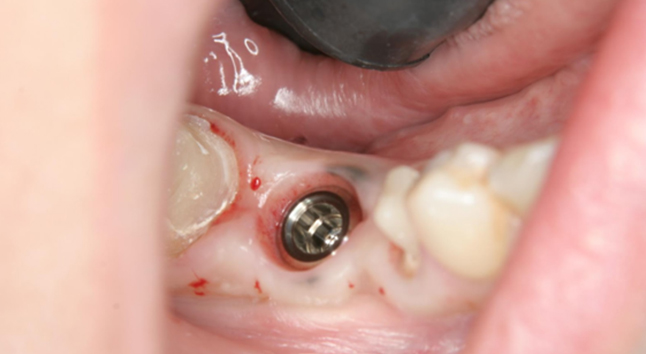

その後、骨にインプラントを埋めて、6週間後に歯型を取りセラミックの歯を作成、更にインプラント部位(赤丸部分)の前後の歯もセラミックで作成し装着しています。